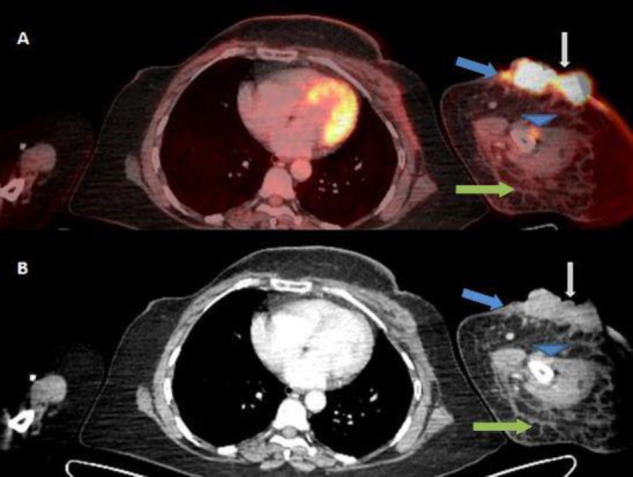

Objectives: Lymphangiosarcoma is a rare tumor that affects the upper limbs of patients who have undergone breast cancer surgery, including axillary dissection, followed by radiation therapy (RT) to the axilla and has a poor prognosis. 18F-FDG PET/CT may enable the earlier detection of malignant transformation in a setting of chronic lymphedema and help evaluate the extent and staging of the tumor, allowing earlier initiation of treatment options.

Case presentation: We herein report a case of cutaneous lymphangiosarcoma in a 47-year-old breast carcinoma patient, which occurred 9 years after initial surgery and radiation therapy. Distant metastases were detected on 18F-FDG PET/CT. The patient underwent fore-quarter amputation of the upper limb and concurrent chemo-radiation therapy. However, she succumbed to her disease after 3 cycles of chemotherapy.

Conclusions: 18F-FDG PET/CT scan helps in the early detection of malignant transformation and lymphangiosarcoma in a setting of chronic lymphedema in breast carcinoma patients following radiation therapy to the axilla. Furthermore, it helps determine the extent of regional spread and detect metastatic involvement, thus enabling better clinical management of these patients.